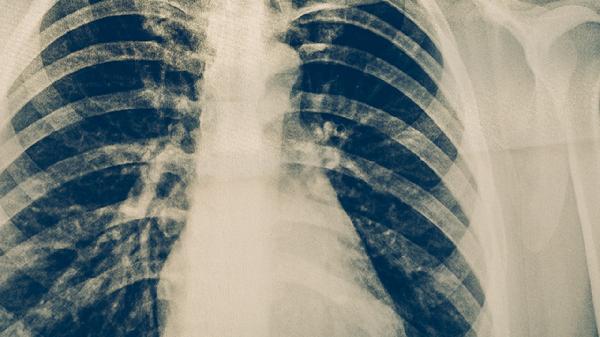

血行播散性肺結核是結核桿菌通過血液廣泛播散至肺部及其他器官的嚴重類型,可分為急性和慢性兩種。急性者起病急驟,表現(xiàn)為高熱、寒戰(zhàn)、呼吸困難;慢性者癥狀較隱匿,可能出現(xiàn)消瘦、持續(xù)低熱。影像學可見雙肺彌漫性粟粒樣結節(jié)。治療需聯(lián)合使用乙胺丁醇片、鏈霉素注射液等藥物,療程較長。

繼發(fā)性肺結核是成人最常見的類型,多由體內潛伏病灶復發(fā)或再次感染引起。病變多位于肺尖或鎖骨下區(qū),可形成空洞、纖維化或鈣化。典型癥狀包括咳嗽、咯血、胸痛等。治療需根據(jù)藥敏試驗選擇利福噴丁膠囊、對氨基水楊酸鈉顆粒等藥物組合,療程通常需6-9個月。